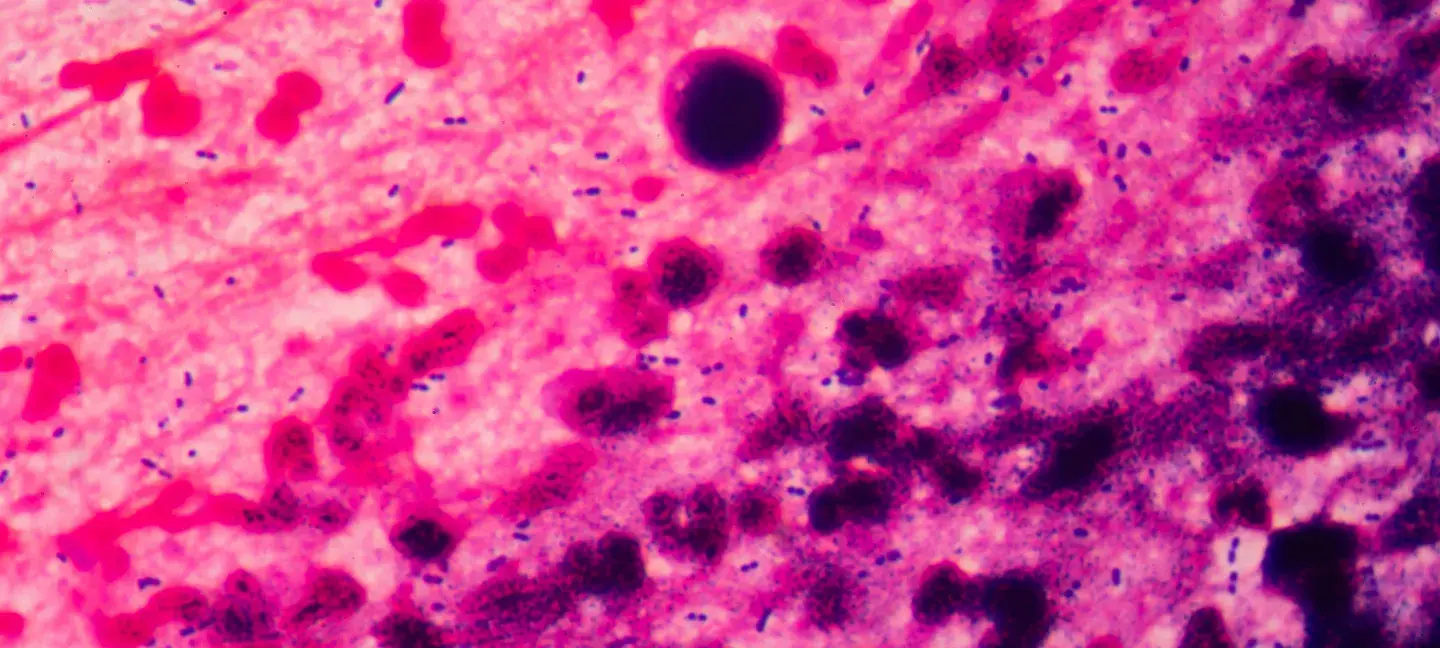

Immunologie - Vaccins - Immunologie

Deze subsidie biedt $ 150.000 voor eenjarig onderzoek dat doorbraken nastreeft in humane immunologie, vaccinontwikkeling of immunotherapie voor mondiale ziekten.

• Fundamenteel en translationeel onderzoek naar het menselijk immuunsysteem

• Ontwikkeling van nieuwe vaccins en immunotherapieën

• Interdisciplinair onderzoek met technieken uit onder meer moleculaire biologie, nanotechnologie, bio-informatica en kunstmatige intelligentie